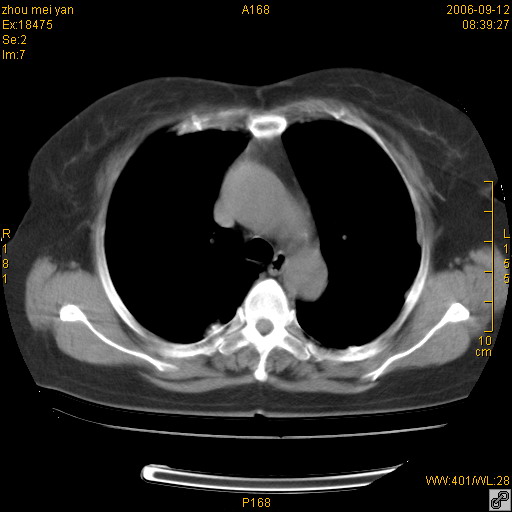

患者、女、55岁。因心率失常住院检查ct发现胸部多发结节。腹部b超肝、胆、胰、脾、肾、子宫附件未见异常。无结核病史,无粉尘接触史。请大家来会诊。谢谢!

病变位于胸膜,多发结节,边界清楚,内见小结节状钙化。其它未见异常。

双侧胸膜多发结节,形态不规则,边缘较清楚,每一个结节中心似乎都有钙化点的特征,与胸膜广基相切。临床无结核病史,无粉尘接触史。

影像表现十分有特点:双侧肋胸膜及膈胸膜广泛散在分布大小在2至6mm左右,较大病灶中心可见钙化。

考虑恶性胸膜间皮瘤可能性大,病灶位于胸膜,以宽基地与胸膜相连,呈结节样改变,部分病灶内可见点状钙化影。请各位老师多多指导!

双侧肋胸膜及膈胸膜广泛散在分布大小不等结节影,较大病灶中心可见钙化。